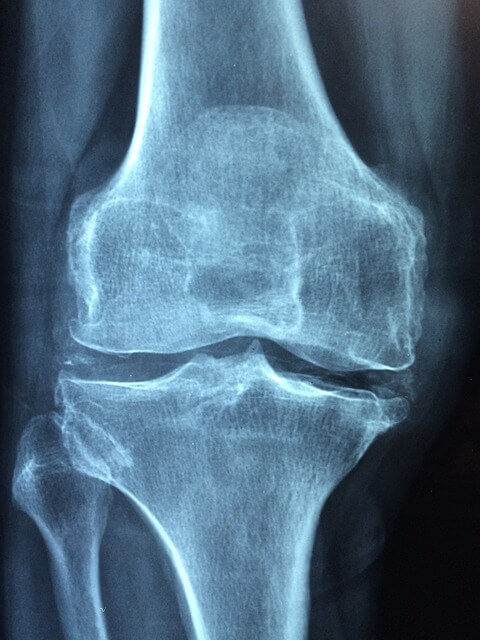

퇴행성 관절염은 어디에 잘 생기나요?

퇴행성 관절염의 경우 관절이 있는 곳이라면 모든 관절에 다 생길수 있습니다.

하지만 특히 무릎 관절, 허리 관절, 엉덩이 관절, 손가락 관절에서 많이 나타나는 질환입니다.